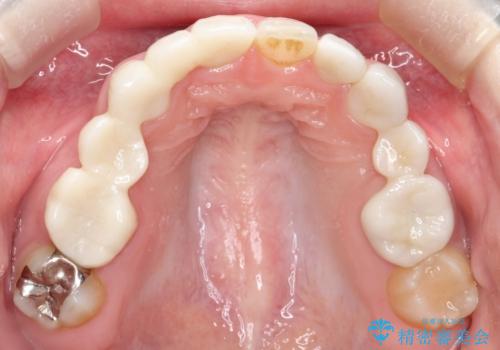

- 保険治療で装着されたかぶせ物と詰め物を変更したいとのことで来院されました。

自然なオールセラミックへ変更することとなりました。

金属を使わないセラミックへ変更することで、自然な見た目になるとともに、ぴったりとした精度の高いかぶせ物を装着することができました。